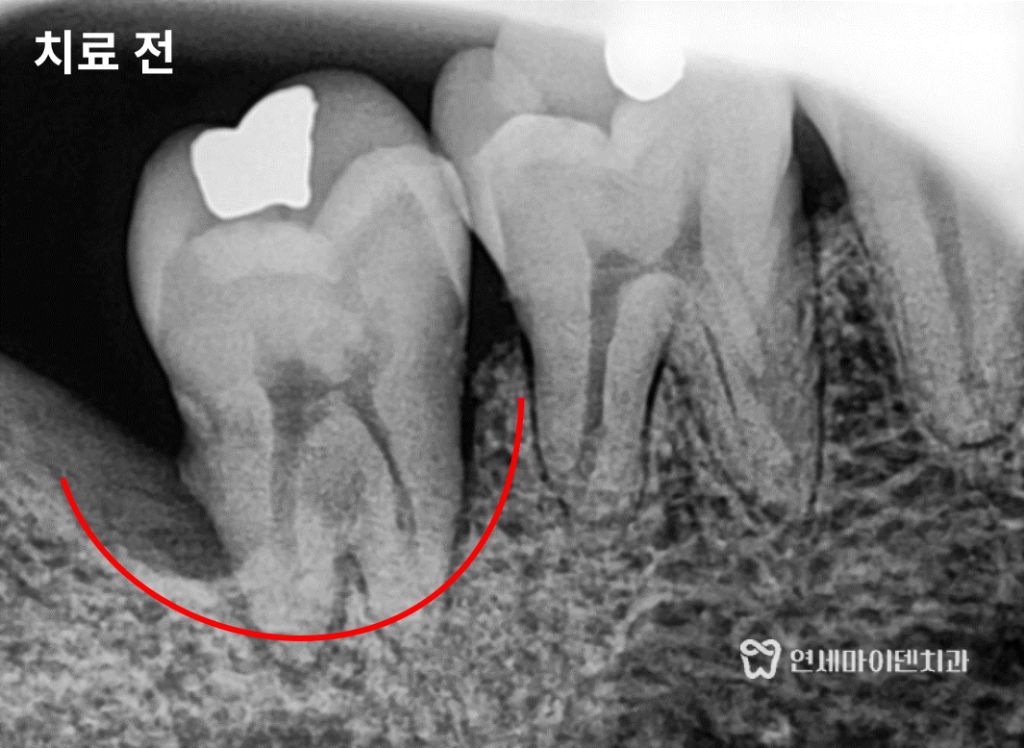

소개해드리고자 합니다.신경치료 후 반복되는 잇몸 염증

환자분은 약 3년 전 신경치료를 받으셨습니다.

신경치료 후에도 몇 달에 한 번씩

잇몸에서 고름이 생기고 터지는 증상이 반복됐다고 하셨습니다.식사에는 큰 지장도 없고 통증도 심하지 않아서

추가적인 치료를 하지는 않으셨습니다.그러던 중 타 치과에서 진료를 보시고

염증이 반복되면 발치 후 임플란트를 해야한다는 소견을 듣고치아를 살릴 수 있는 방법은 없는지

저희 병원을 찾아오셨습니다.

진단 결과, 문제는 기존 신경치료가 완전하게 이루어지지 않아서

치아 뿌리 끝에 염증이 남아있었고그로 인해 뿌리 중간 부위의 치조골이 녹아 있는 상태였습니다.

이러한 경우는 치아에 금이 가 있을 가능성도 높기 때문에

단순한 재신경치료만으로는 치료가 어려울 수 있습니다.염증으로 녹은 뼈, 살릴 수 있을까?